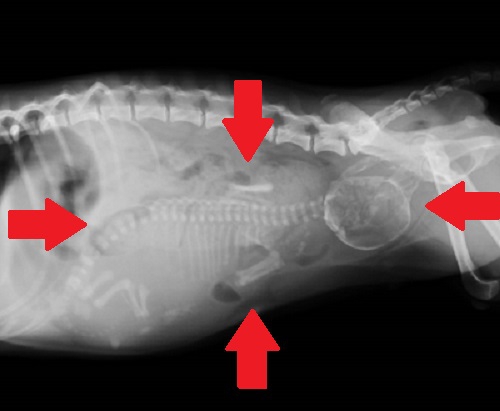

飼い主さんも気づかずに妊娠、突然の破水で緊急来院しました。胎児数は1頭で妊娠期間を大幅に過ぎているようです。胎児はお母さんの子宮内であまりに大きくなりすぎて、骨盤に引っかかってもはや産道から出ることができません。下のレントゲン写真で、お腹の大きさぎりぎりまで大きくなった胎児が確認できます。